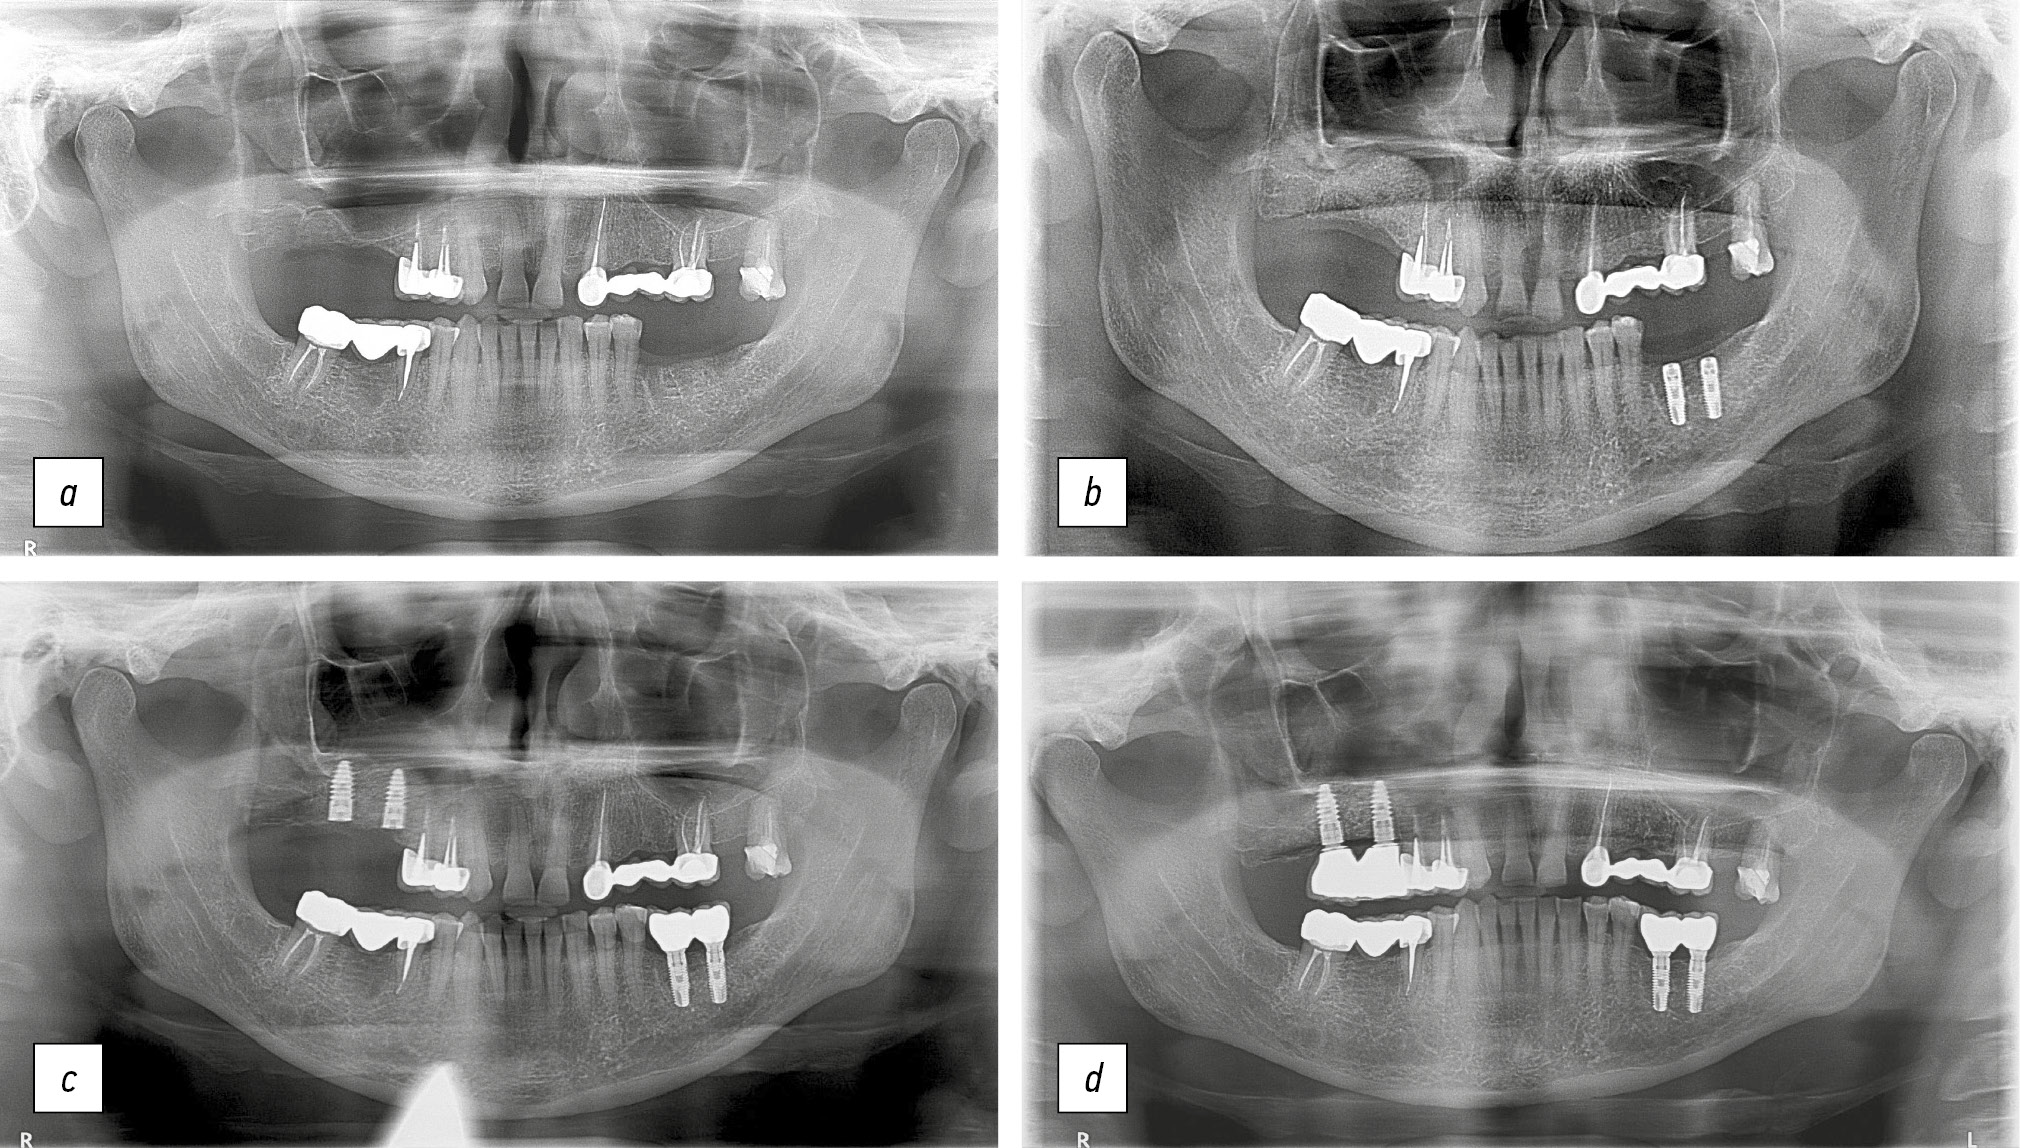

В качестве клинических примеров приводим ортопантомограммы пациента Ч. и пациентки Б. до и после аугментации лиофилизированной губчатой костной тканью (рис. 5, 6).

Рис. 5. Ортопантомограммы пациента Ч.: a — исходная клиническая ситуация; b — проведена аугментация с использованием лиофилизированной губчатой костной ткани; c — установлены дентальные имплантаты, этап остеоинтеграции; d — клиническая ситуация через 3 года.